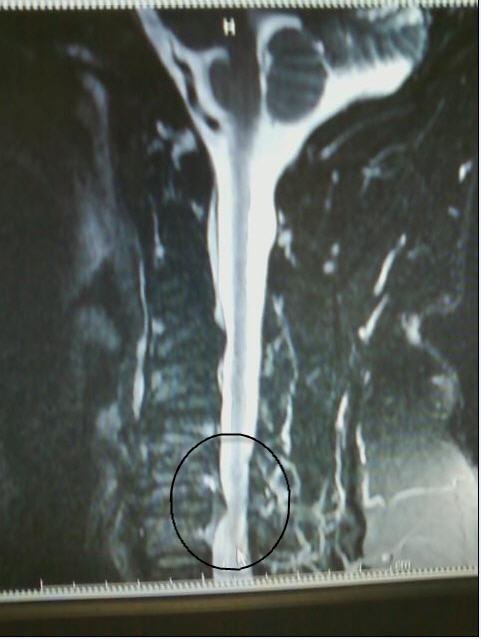

I know this is bordering on TMI, but if you have ever wondered what your spine should NOT look like....